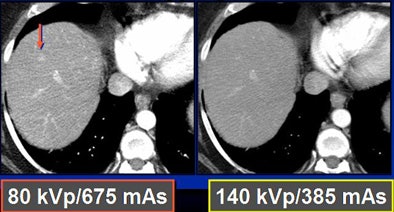

Because low kVp is closer to the K-edge of iodine, the attenuation of iodine structures increases as kVp decreases. Thus, a CT image of an iodine structure imaged at 140 kVp is about 200; dropping the kVp to 80 nearly doubles the attenuation, even though tube energy is reduced, Nelson explained.

In a phantom model tested by the Duke team, iodine structures were seen more clearly when attenuation was reduced. Similar results were found in patients with hepatic lesions; some subtly hyperenhancing liver lesions could be seen only at lower kVp levels.

To test the hypothesis quantitatively, Duke researchers performed a study of 48 patients with 68 hyperenhancing live lesions, scanned using a dual-energy volume technique (GE Healthcare, Chalfont St. Giles, U.K.) during the arterial phase, Nelson said. One rotation was scanned at 80 kVp and 540 mAs; a second was acquired at 140 kVp and 308 mAs. The results showed significant differences in lesion conspicuity with the use of low-kVp imaging.